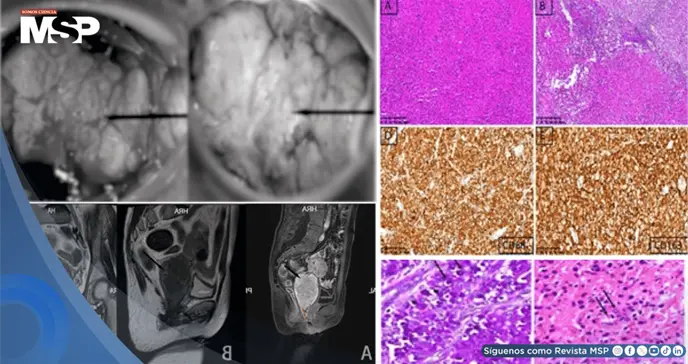

Durante la exploración ginecológica se identificó una masa de 5 x 5 cm con aspecto de coliflor en el labio anterior del cuello uterino, que sangraba fácilmente al tacto. Los estudios de imagen mostraron un cuello uterino aumentado de tamaño con formación de tumor sólido, generando alta sospecha de malignidad.

Inicialmente, la presentación clínica sugería un tumor maligno cervical. Sin embargo, el estudio histopatológico reveló hallazgos característicos de malacoplaquia, una enfermedad inflamatoria rara.